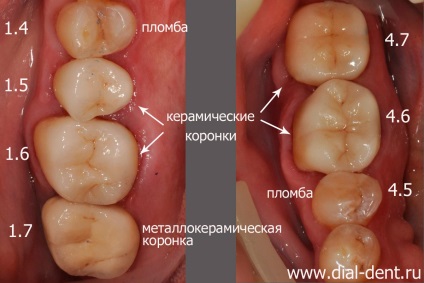

Problema: Pacienta de 58 de ani a apelat la clinica, „Dial-Dent“ pentru tratament stomatologic complex. Pe dinții de umpluturi vechi, cioplit în locuri, sub sigiliile cariilor. A fost necesar să-și petreacă tratamentul și recuperarea a șapte dinți (dreapta maxilarului inferior și superior).

Soluție: au fost tratate canale sub microscop. tratarea cariilor, restaurate umpluturile dinti si coroane (dinti 1,4, 4,5 - obturațiilor ușoare, 1.5, 1.6, 4.6, 4.7 - 1.7 coroane ceramice -. cape de coroane și metaloceramice).

Planul de tratament pe fotografiile originale ale dinților:

Dinții 1.4, 4.5 - sigiliu de lumină.

Dinții 1.5, 1.6, 4.6, 4.7 - coroane ceramice.

1.7 dinte - cape coroană și cermet.